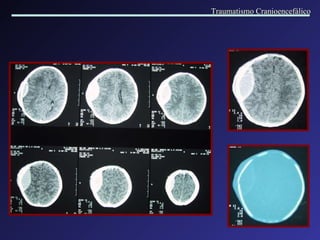

Edema Cerebral Difuso D iminuição dos ventrículos e apagamento das cisternas. Colabamento dos ventrículos e das cisternas. Perda da diferenciação entre substância branca e cinzenta . Traumatismo Cranioencefálico